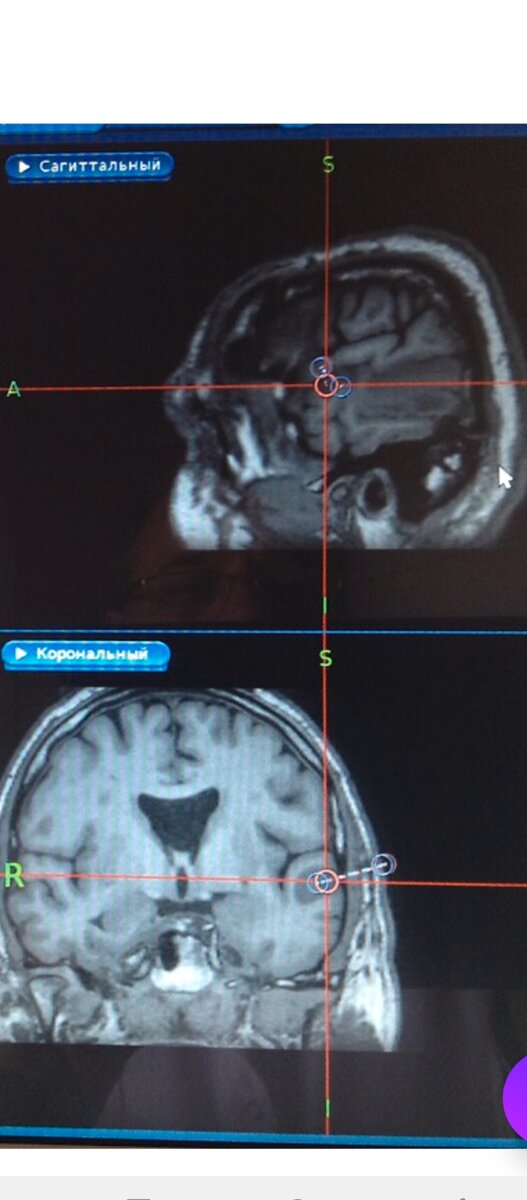

В Питере в медицинском университете им. Павлова работает доцент кафедры нейрохирургии Олег Викентьевич Острейко.  Он разработал новый метод лазерной операции-"малоинвазивная лазерная гипертермия" и уже запатентовал его.  Раковые клетки лишаются жизнеспособности путём нагрева лазерным лучом.  Операция выполняется через маленький разрез(12-15мм) и дальше из него входят в опухоль и облучают её.  Со временем опухолевая ткань рассасывается.  Для улучшения результата дальше проводят курсы химиотерапии или лучевой терапии. Поскольку операция щадящая, то пациенты через несколько часов уже могут ходить, а через 3 дня их выписывают домой.  Но у этой операции есть противопоказания-размер больше 4-5 см и если опухоль находится в стволе мозга.  Полезный опыт перенимают нейрохирурги из Нижнего Новгорода, но выполняются операции пока только в Санкт-Петербурге.  Метод позволяет уменьшить размеры опухоли. Применяется при начальной стадии глиом и глиобластом, а также при глубокой локализации, когда отк

Применяется при начальной стадии глиом и глиобластом, а также при глубокой локализации, когда открытое удаление не целесообразно из-за высоких рисков.